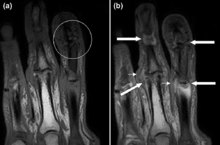

Magnetic resonance images of the fingers in psoriatic arthritis. Shown are T1 weighted axial (a) pre-contrast and (b) post-contrast images exhibiting dactylitis due to flexor tenosynovitis at the second finger with enhancement and thickening of the tendon sheath (large arrow). Synovitis is seen in the fourth proximal interphalangeal joint (small arrow).